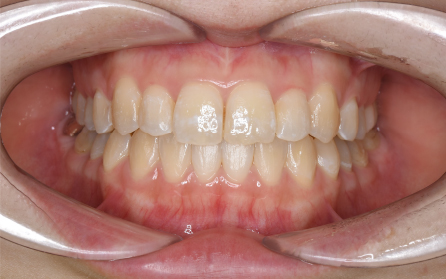

19歳 女性

主訴 「前歯のでこぼこを治したい」

診断 「両側側切歯のクロスバイトを伴う叢生症例」

上下前歯部の叢生の改善のため、歯と歯の間を0.5mm程度削ってスペースを確保しながら歯を並べました。患者さんの協力(マウスピースの使用状況等)も良好で、前歯が前方に突出することなく側切歯(2番目の歯)のクロスバイトも改善されました。前歯が突出しないように治療計画をたてないと口唇が閉じにくくなったり、口元がもっこりしてしまいます。治療期間は18か月でしたが、動的治療後は歯を安定させるために保定装置の使用が必要です(最低2年)。矯正治療では患者さんの協力が非常に重要であり(特にマウスピース矯正の場合は使用時間)、治療結果や治療期間に影響します。また、歯の移動にはワイヤー矯正、マウスピース矯正にかかわらず歯根吸収、歯肉退縮、歯髄壊死のリスクがあります。